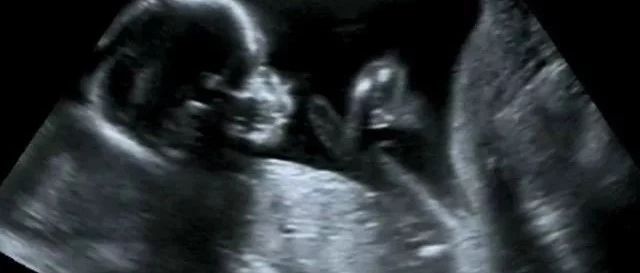

孕期准妈妈要做的产前检查项目有很多,如多次B超、唐筛、糖耐等,其中有一项非常重要的检查就是“大排畸”